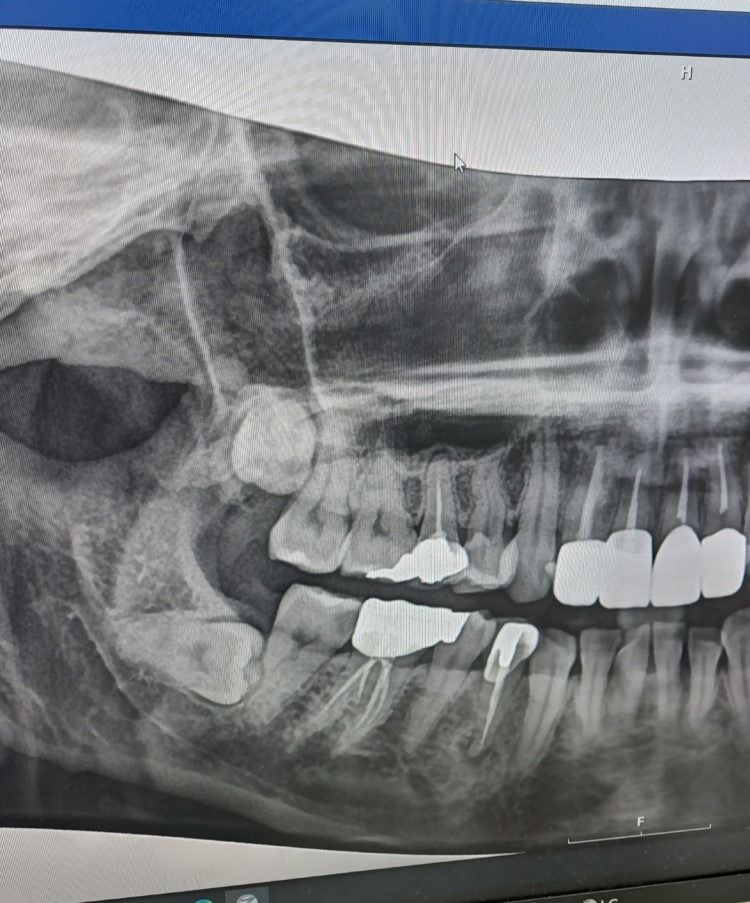

아랫쪽사랑니 꼭 빼야되는모양인가요.

잇몸밖으로는 아예 나오지 않은 매복사랑니인데.

앞에 어금니 뿌리 건드는거같은데 사진이겹쳐보이는 가능성도

있지만 지금안뽑으면 나중에 어금니도 같이뽑게되니

지금뽑아야된다는 종합병원. 지금 뽑아도 사랑니옆어금니가 공간때문에 뽑고나서 흔들리거나 하게되면 어금니도뽑을가능성이 있다길래.

저정도 사랑니라면 잇몸뼈에 뭍혀진 상태인거 같습니다. 저도 아직 불편감이 없다면 발치를 하지 않으셔도 크게 문제가 없다고 생각됩니다.